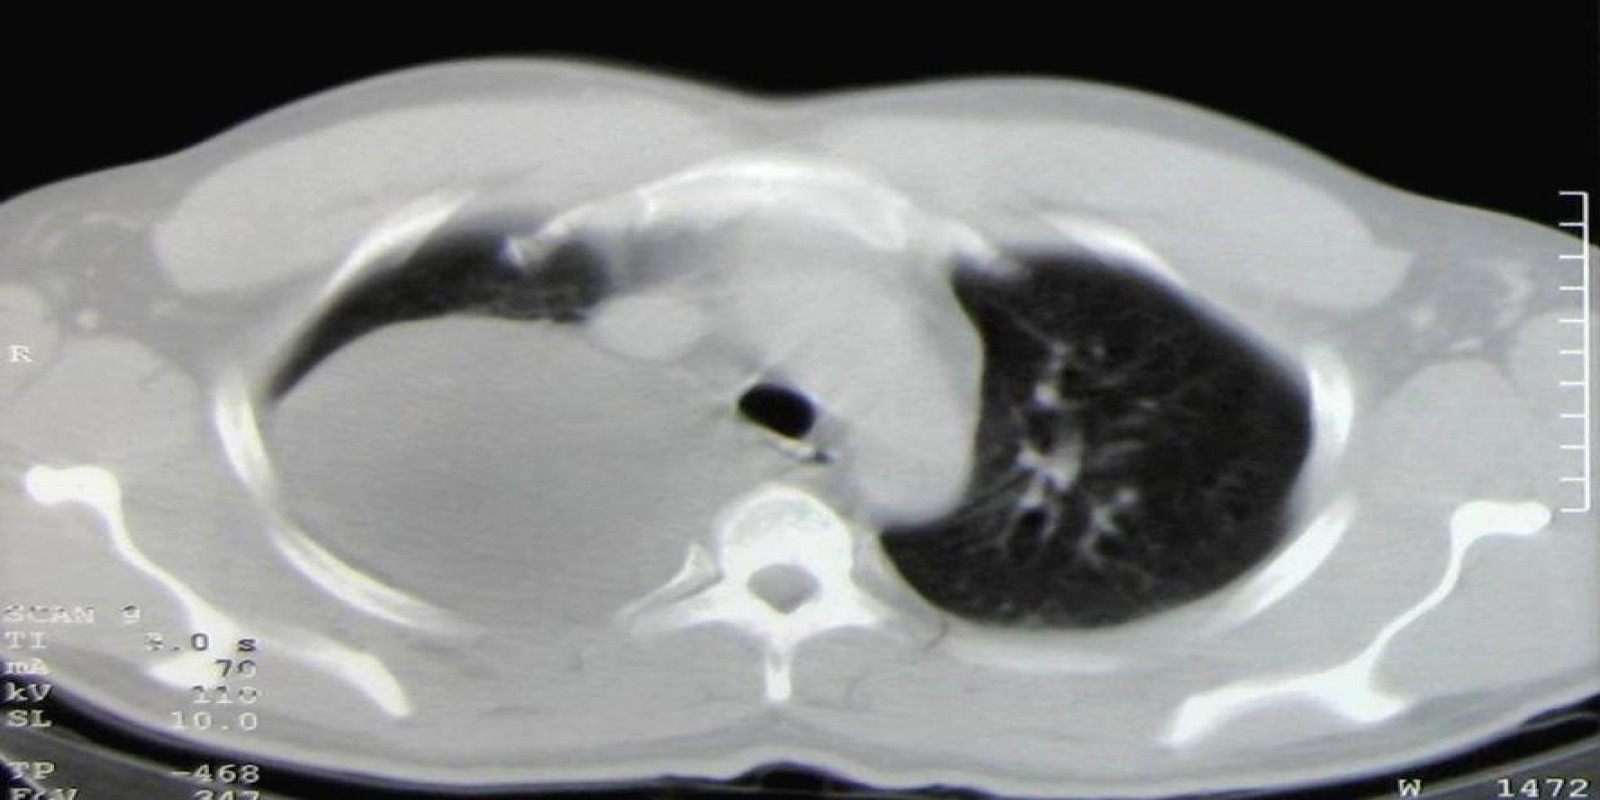

Ganglioneuroma mediastinal

Mediastinal Ganglioneuroma